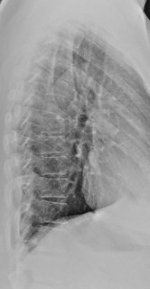

おまけにわたしの灰のレントゲン貼っておこうかな。

見ても、何が悪いのかぜ~んぜんわかりません~。

見たくなかったですよね?(笑)